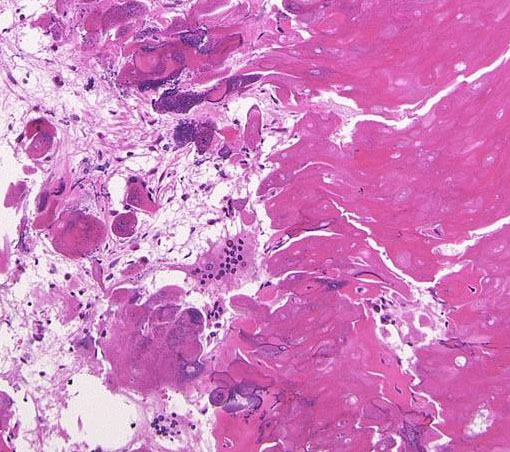

Monomorphous mass of well-differenciated squamous epithelium lacking surface maturation and wet keratin.

摘出した骨化片の病理像です。成熟した骨組織 mature boneです。

adamantinomatous typeです。mature boneの端には破骨巨細胞が多数見られます。

鞍内にあった部分の病理所見です。adamantinoomatous typeで,破骨細胞を伴う強い骨化がみられます。